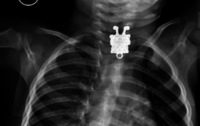

Por qué los niños no deben jugar con objetos pequeños: Bob Esponja hallado en el esófago de un niño

Salud infantil"Mucho cuidado con las cosas pequeñas", se les suele decir siempre a los padres. "No lo dejéis solo", "Atentos a los momentos de silencio, pues será entonces cuando haga las peores cosas", se añade. Y es que tienen una increíble facilidad...